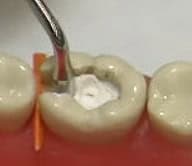

การเคลือบหลุมร่องฟัน เป็นการใช้ฟลูออไรด์เหลวสีขาวมุก นำมาทาลงบนด้านบดเคี้ยวของฟัน หรือตามหลุมร่องฟันที่ลึกและแคบโดยเฉพาะฟันกราม เพื่อป้องกันฟันผุ โดยทั่วไปฟันมักจะผุตามหลุมร่องฟันก่อนผุบริเวณผิวเรียบ เพราะหลุมร่องฟันนั้นลึก ยากแก่การเข้าถึงของขนแปรงสีฟัน น้ำยาบ้วนปาก จึงง่ายต่อการอาศัยอยู่ของแบคทีเรียซึ่งก่อให้เกิดฟันผุ ดังนั้นควรเคลือบหลุมร่องฟันไว้ก่อนที่จะเกิดฟันผุ จะเป็นการป้องกันที่ดีที่สุด และเก็บรักษาฟันที่คุณรักให้สมบูรณ์แข็งแรง